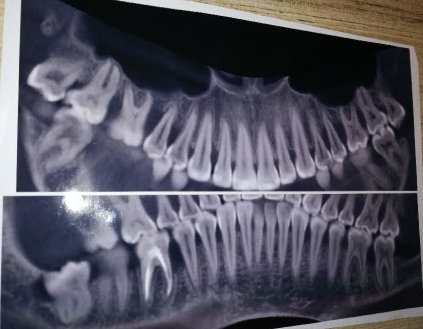

Мне 29 лет. Ставят сильнейший пародонтоз. Прогрессирует разрушение костной ткани, шатается верхняя 5-ка справа и по-моему нижняя тоже. Десны уже не просто кровоточат, а вздуваются в разных местах, как воздушные шарики. Вчера вскрывали флюс. Даже на открытый кюретаж, который отправили сделать, не могу пойти, т.к. десна в нестабильном состоянии, при этом анализы (гормоны, кальций, сахар) все в норме. Сказали кроме кюретажа, необходимо сначала депульпирование нижних зубов, иначе потеряю их. И депульпировать те зубы, которые шатаются (5-ка нижняя и верхняя справа) + шинирование и уколы в десны.